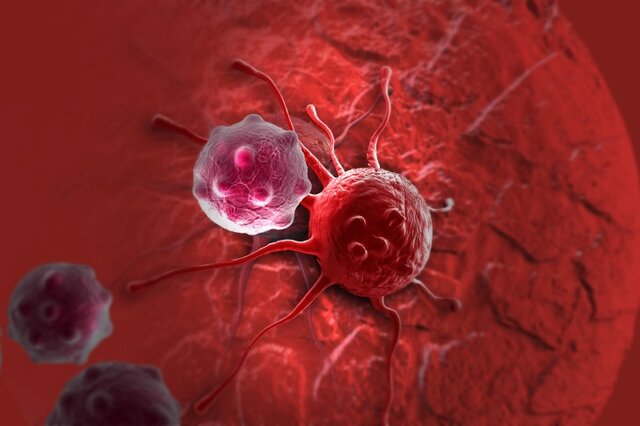

این نوع از سرطان استخوان در یاخته های غضروفی شکل می گیرد و دومین سرطان شایع استخوان است.

روش های عکس برداری می توانند به تعیین محل و اندازه ی تومورهای استخوان و گسترش یا عدم گسترش آن ها به سایر نقاط بدن کمک کنند. در این مقاله با علائم سرطان مغز استخوان و نیز روش های درمان آن آشنا می شوید. یک تومور رشد غیر طبیعی بافت در بدن است. سلول های توموری توانایی تنظیم کردن ندارند بنابراین سلول های بیشتری تولید می کنند و منجر به تشکیل یک توده می شوند در حالی که بسیاری از تومورها سرطانی.